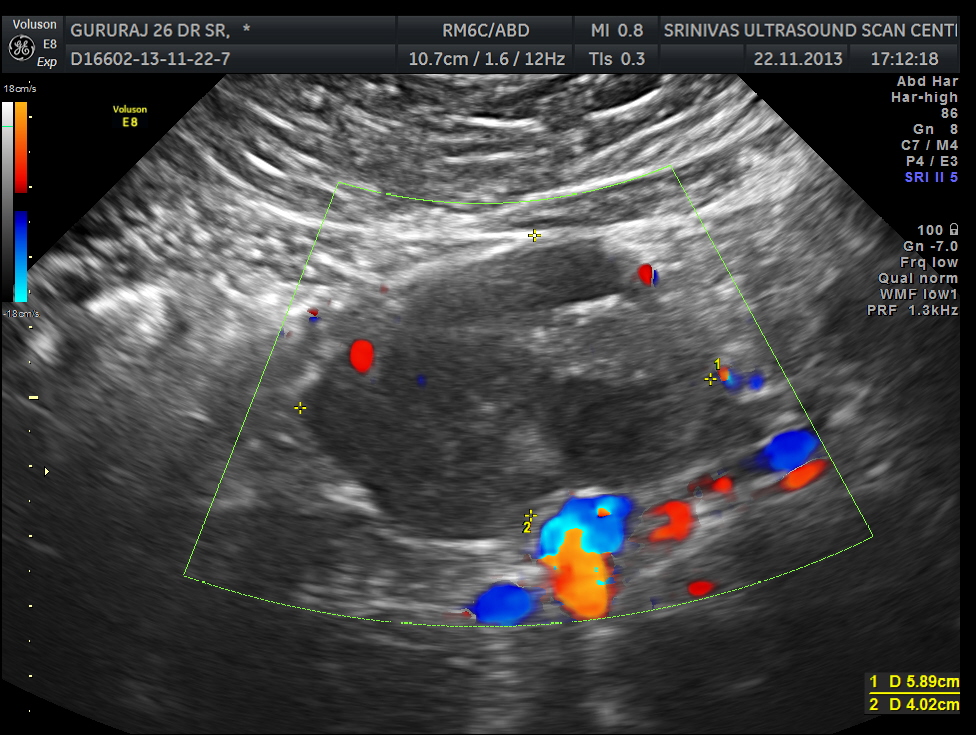

Now for the unexpected findings . To finish off the scan , I was sweeping the aorta, IVC and the pre and post aortic regions.

The following image was obtained with the transducer in the mid epigastric region and an inch to the left of the mid line.

This mass visualised there . This was antero-lateral to the aorta and showed mixed echotexture , with some vascularity.

This was not mobile and all i could offer was a description of what was seen with the impression of a mass of unknown origin – ?? enlarged node and advised further work up.

He underwent a contrast CT and was found to have a mass arising from the intestinal wall. He underwent surgery subsequently and the mass was removed . It was a benign leiomyoma arising from the jejunal wall and showed some erosions on the inner aspect ( cause for the anemia ) . Now came the pleasant surprise for everybody.His anemia improved and his headaches disappeared totally. The explanation offered was reactive thrombocytosis due to the anemia probably caused the hemicranial pain and when that was taken care of he was better.

Many others looking at the ultrasound image could have probably guessed the pathology. But I was happy that at least I picked up the mass , which led to the other things.